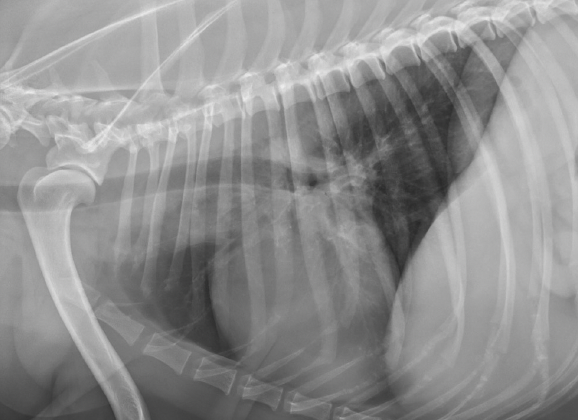

Critiquez l’exposition de cette rx

a) elle est adéquate

b) elle est sous-exposée

c) elle est surexposée

d) l’appareil est défectueux

A

Ici il s’agit d’une rx pour visualier la vessie (blocages/calculs). L’effet noir ne permet pas une distinction claire des régions anatomiques, ce qui signifie que l’image rx est surexposée